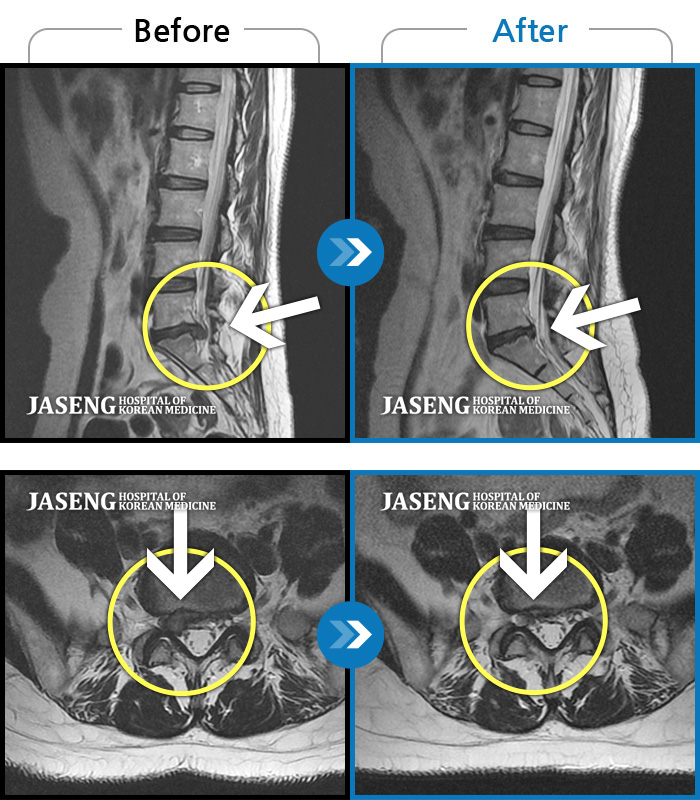

ȯںп Ǹ ǿ ԿǾ, ο ġ ۿ Ƿ ġḦ Ͻñ ٶϴ.